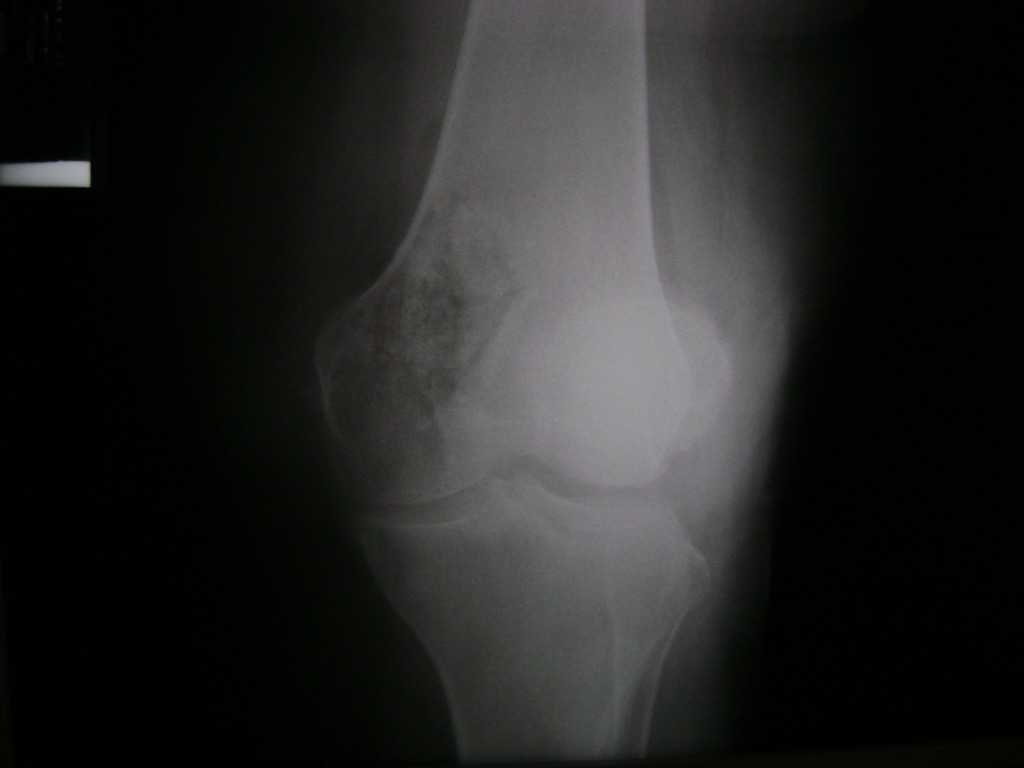

Fémur - Rodilla